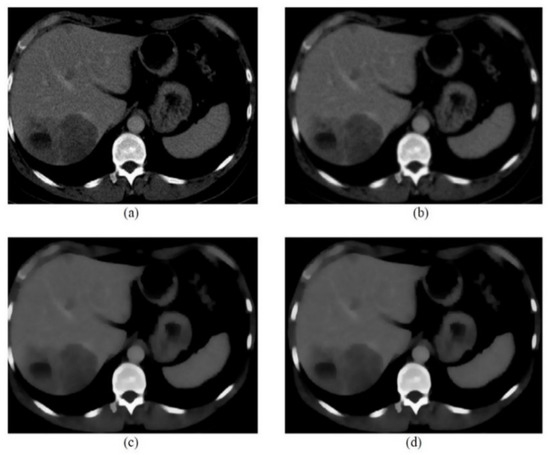

| CT image (Figure 6) 256 × 256 | 26.01 | 0.05 |

| CT image (Figure 7) 256 × 256 | 20.15 | 0.1 |

| CT image (Figure 8) 256 × 256 | 20.13 | 0.1 |

| CT image (Figure 9) 256 × 256 | 26.09 | 0.05 |

| CT image (Figure 10) 256 × 256 | 20.18 | 0.1 |

| CT image (Figure 11) 256 × 256 | 26.15 | 0.05 |